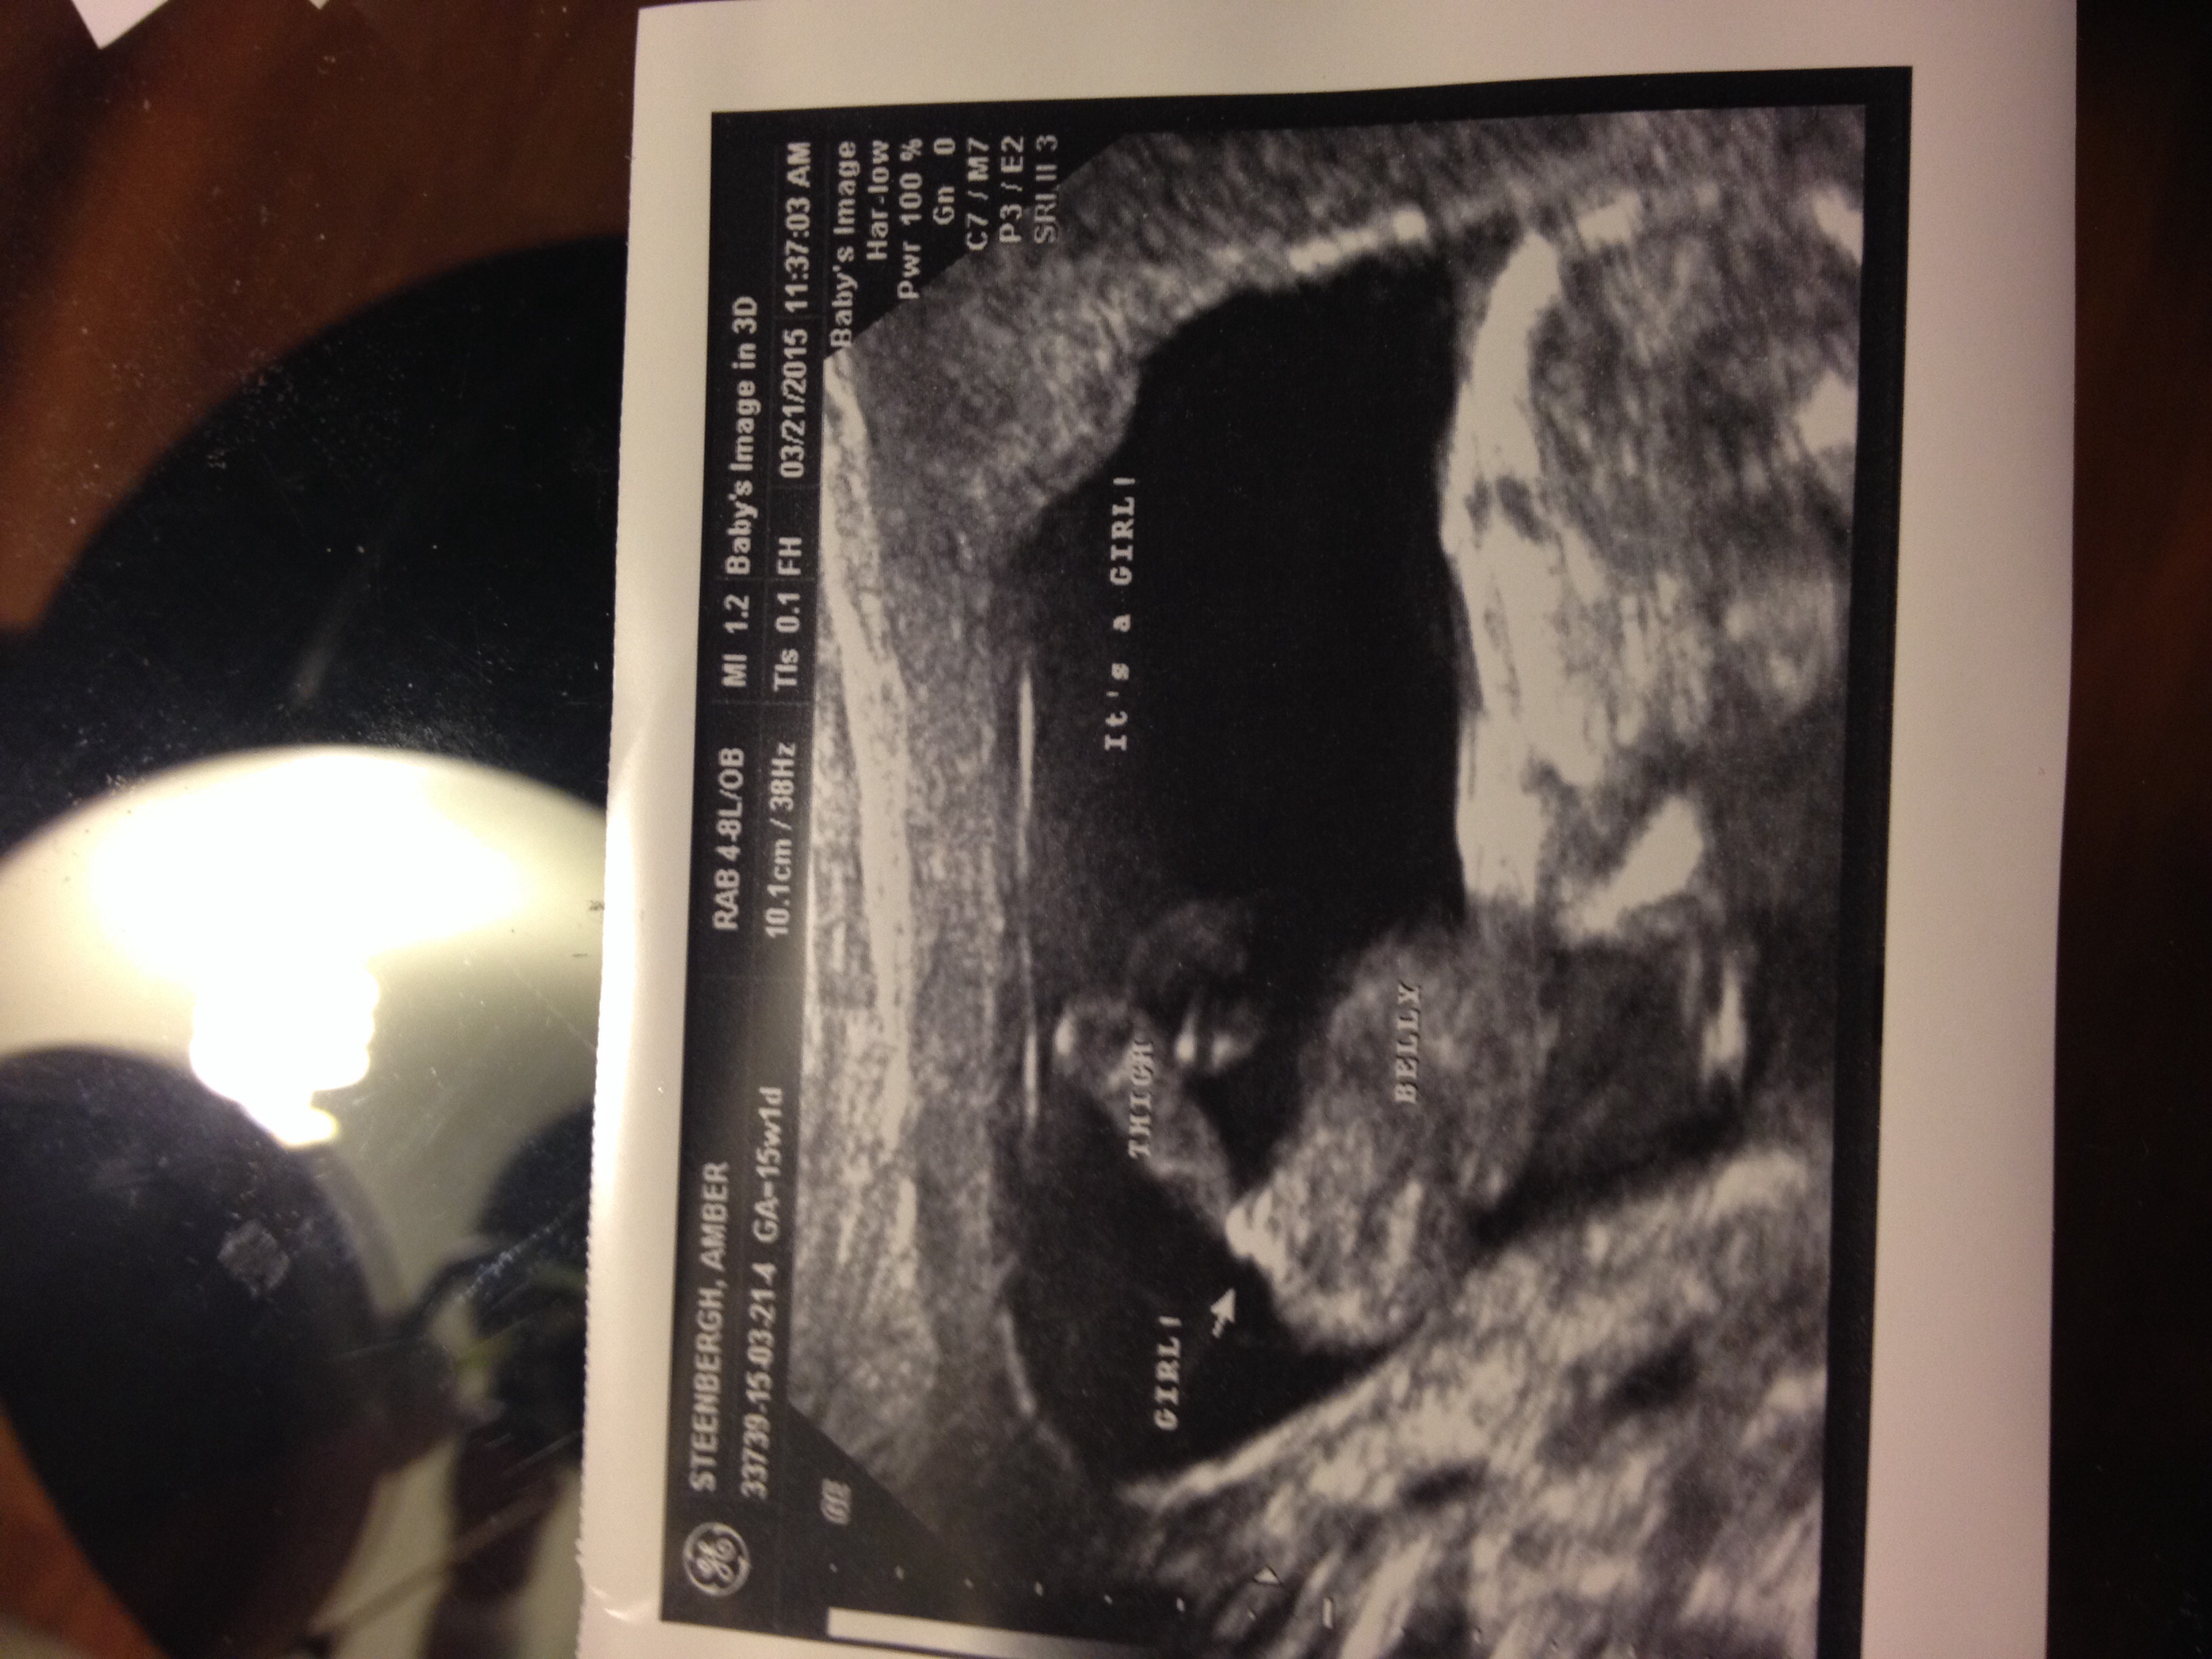

This is our first baby, we were hoping for a little princess since there are only boys so far, my mom has 7 grandsons and my husbands parents have 4 grandsons so far. We were so eager to find out that we went to a 3d ultrasound place and we were told GIRL at 15 weeks!!' What do you guys think?!Attachment 24725